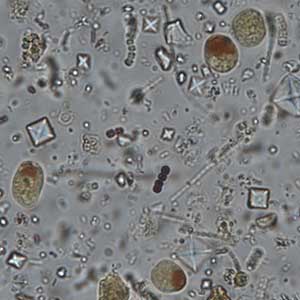

Les kystes de Iodamoeba butschlii sont ovalaires, à noyau rond, de diamètre moyen à grand, avec un nucléole large central à périphérique ; ce dernier n’est cependant pas toujours visible. Ils sont caractérisés par une vacuole iodophile volumineuse, excentrée, qui se colore franchement au Lugol, apparaissant brun-acajou. Ils mesurent 5 à 20 μm de longueur (Euzéby, 2008).

Les kystes de Iodamoeba butschlii sont en général facile à mettre en évidence par coloration de la vacuole iodophile au Lugol. Le diagnostic différentiel comprend les amibes de taille petite à moyenne dont les formes immatures d’Entamoeba histolytica qui peuvent aussi présenter une vacuole iodophile (Euzéby, 2008). Néanmoins, ces kystes immatures sont arrondis, ils présentent un à quatre noyaux de type Entamoeba, la vacuole iodophile, si elle existe, est moins colorée au Lugol, et ils possèdent des cristalloïdes que n’ont pas les kystes de Iodamoeba butschlii (Euzéby, 2008). Ces détails sont davantage visibles par coloration au trichrome ou à l’hématoxyline ferrique.